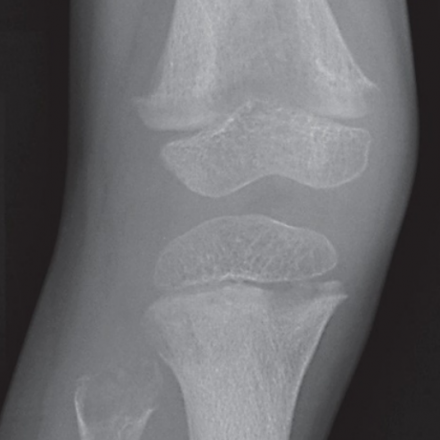

The x-ray abnormalities seen in the bones are characteristic of HPP for many patients with the childhood form and the most severe perinatal or infantile forms. Still, these characteristics may not be recognized as diagnostic of HPP even by experienced radiologists. Knowing which x-ray features to look for to help diagnose HPP is of key importance. These features are illustrated in medical books and articles. However, patients with odonto HPP (the common form of HPP that affects only the teeth) do not have bone disease including these x-ray findings.

Screenshot (477)

Classic Changes of Childhood HPP